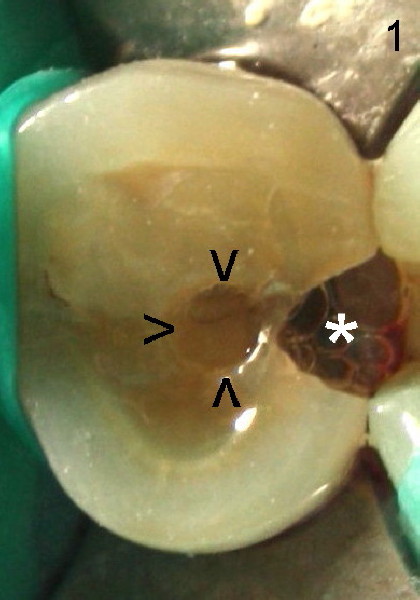

A 50-year-old oriental lady comes to our clinic with chief complaint "I have toothache after filling comes out. Can you just place a filling back?". She had RCT done in her home country. Exam shows that the upper right 2nd premolar (#4) has DO caries (* in Fig.1 (mirror view after placement of rubber dam) ) and occlusal composite (arrowheads). This tooth has severe percussion and moderate mobility. X-ray confirms the DO carious lesion (Fig.2 *). It appears that root canal filling is short (between red and blue arrowheads) and that the filling is not solid. There is a space lateral to the filling (black arrowheads). It seems logical to redo the RCT by removing the old RC filling, extending debridement to the apex and condensing the space better. On re-opening the access, the situation is quite different. Can you guess what it is?